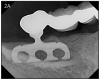

Figure 25 – Radiograph showing significant bone loss around the implant, one year after placement

Figure 25